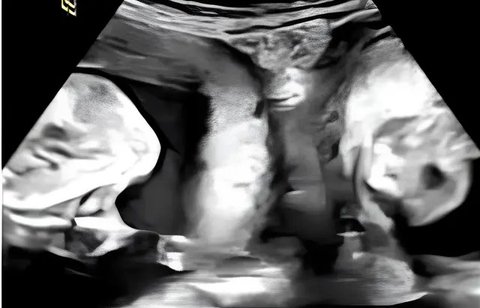

Awalnya Didiagnosis Punya 3 Bayi dalam Kandungannya, tapi Wanita Ini Terkejut saat Cek ke Dokter Lagi

Seorang wanita berusia 25 tahun yang awalnya diberitahu bahwa ia mengandung tiga bayi, tapi ternyata tidak hanya tiga bayi.